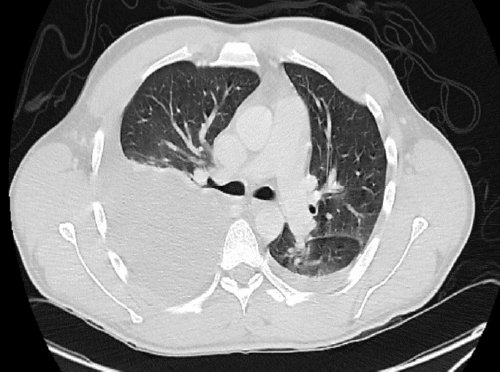

Upon arrival, the primary survey showed normal vital signs and a Glasgow Coma Scale (GCS) of 15. A secondary survey revealed tenderness in the right hemiabdomen and flank, but the abdomen was soft without signs of generalized peritonitis. A Focused Assessment of Sonography for Trauma (FAST) performed in the trauma bay detected fluid in the right upper quadrant and a significant amount of blood clots in the bladder (Figure 2). Initial lab tests showed a hemoglobin level of 13.4 g/dL, elevated white blood cell count (33,400), slightly elevated creatinine (1.20 mg/dL), and elevated liver enzymes (AST: 662 U/L, ALT: 397 U/L).

Figure 2. Focused Assessment with Sonography for Trauma (FAST) Images. Published with Permission

A) Significant clot burden within the bladder

B) Fluid collection in the right upper quadrant